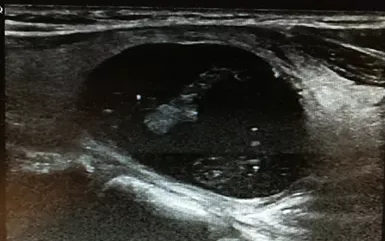

图1 甲状腺良性结节消融前纵切位 30×22×20mm

彩超:左侧甲状腺内可见大小30×22×20mm囊实性包块。

中年女性,45岁,发现左侧颈部包块1年余入院。

查体:左侧甲状腺可触及大小3cm左右包块,质地韧,可以随着吞咽上下活动,无明显压痛。

术前细胞学穿刺:见滤泡上皮细胞及多核巨细胞,细胞无明显异型性,良性甲状腺结节。